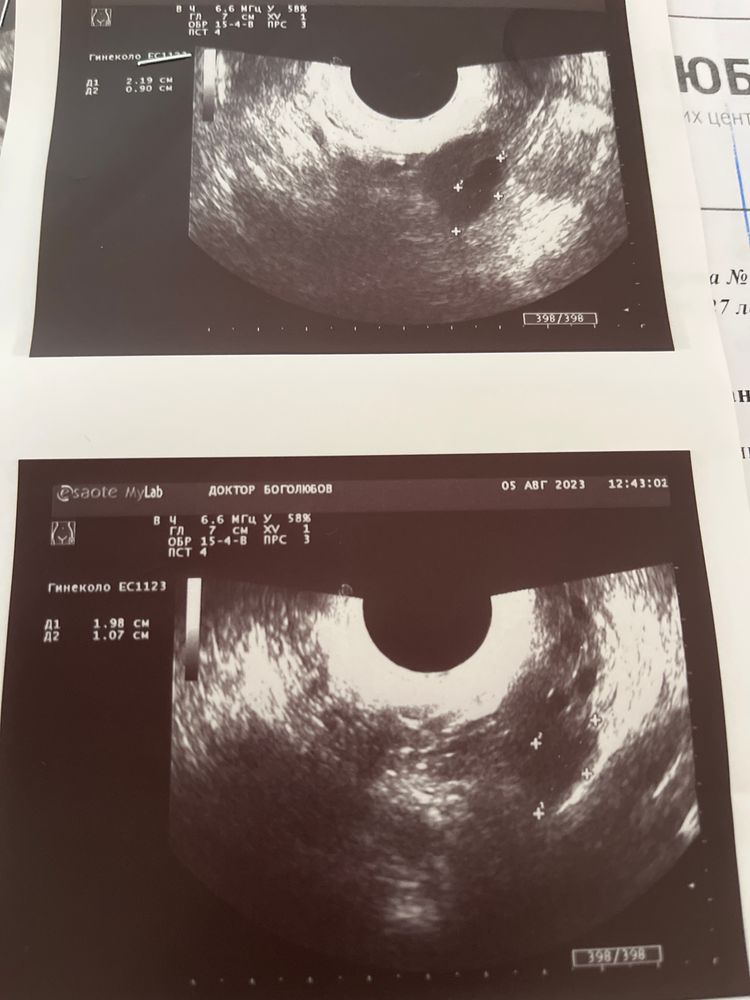

была на узи на 20 дц (так как с мужем ездили в отпуск, не могла сделать раньше) сказали что-то видят в правом и левом яичниках. Вроде как доминантные фолики, а вроде и желтое тело, или вообще «может это дырочки после дриллинга». Этот узист вызвал у меня недоверие, я пошла на сл. День в другую клинику и сделала узи там. Врач сказала, что не видит никаких ДФ и что овуляции вообще не было, и жидности в позадиматочном пространстве нет. Эндик всего 6мм. Узи подкрепляю. На третьем фото узи на 21 дц. Подскажите пожалуйста, что это было?

Я вижу четкое ЖТ и мелкие фоллики по периметру. Неправильная форма, неровный контур. И размер хороший. Жидкость определяется. Это ЖТ.